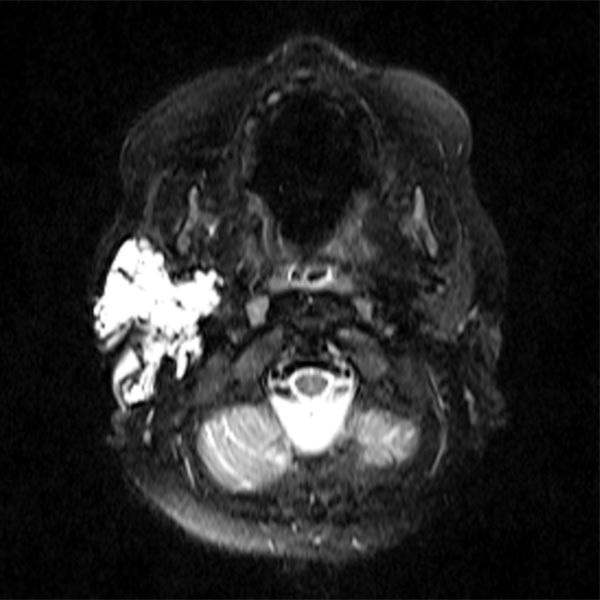

Mixed macrocystic and microcystic lymphatic malformation in the area of the parotid lobe on the right around the ear imaged in a T2-weighted, fat-saturated transverse MRI plane.